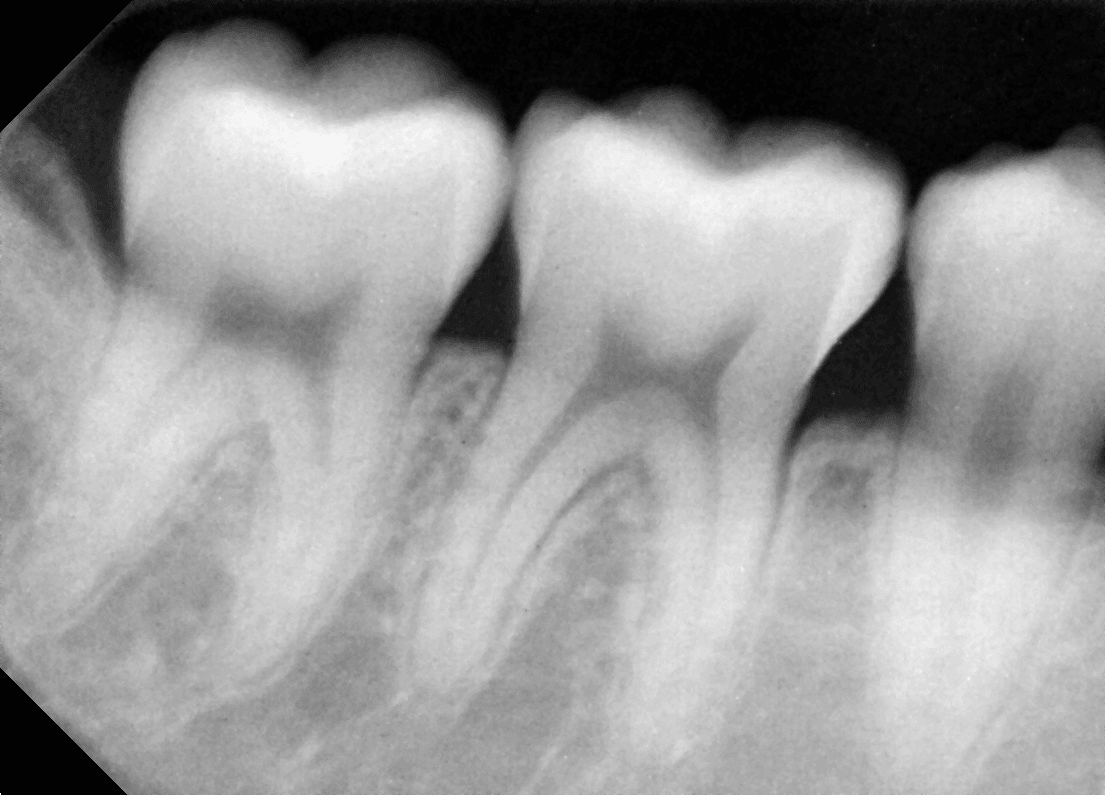

사랑니가 거꾸로 누워있는데 발치하면 시간이 얼마나 걸리나요? (부산 30대 초반/남 거꾸로 난 사랑니 발치)

거꾸로 누운 사랑니(역위 매복 사랑니)는 발치 난이도가 높은 편에 속합니다.

발치 시간에 영향을 주는 요소는

신경과의 거리

치아 뿌리 개수와 형태

잇몸과 뼈에 묻힌 정도

염증 유무, 이런 요소들을 종합해 판단합니다.

CT 촬영 후 계획이 잘 세워진 경우에는 20~40분 내외로 끝나는 경우도 많습니다.

중요한 것은 시간보다도 안전하게, 신경 손상 없이 발치하는 것입니다.